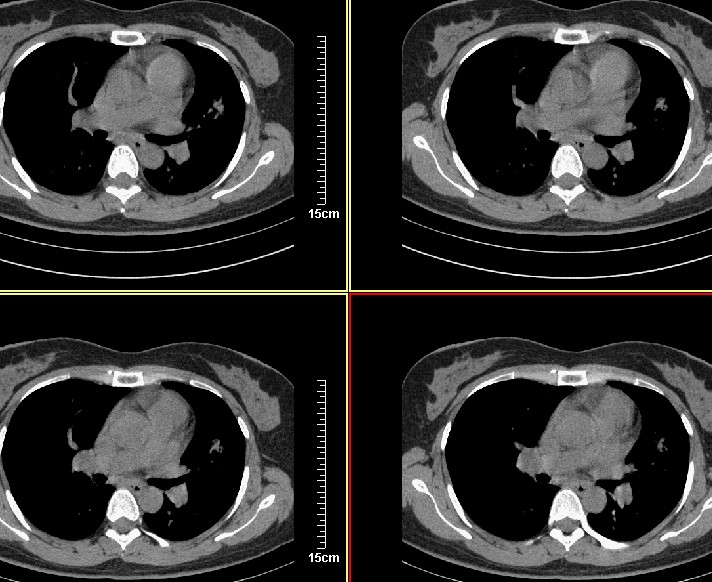

标题: CT8248B:女45岁,三天后复查,经支气管镜注药,会不会是肺 [打印本页]

标题: CT8248B:女45岁,三天后复查,经支气管镜注药,会不会是肺

应该能确定是恶性病变,三天前周围出现的淡薄景应该是肺泡内积血

能不能说说当时灌注的都是什么药吗? 不过从现在的片子看 还是考虑肿瘤    并肺门淋巴结转移

病变密度高实变率高不能排除肺癌